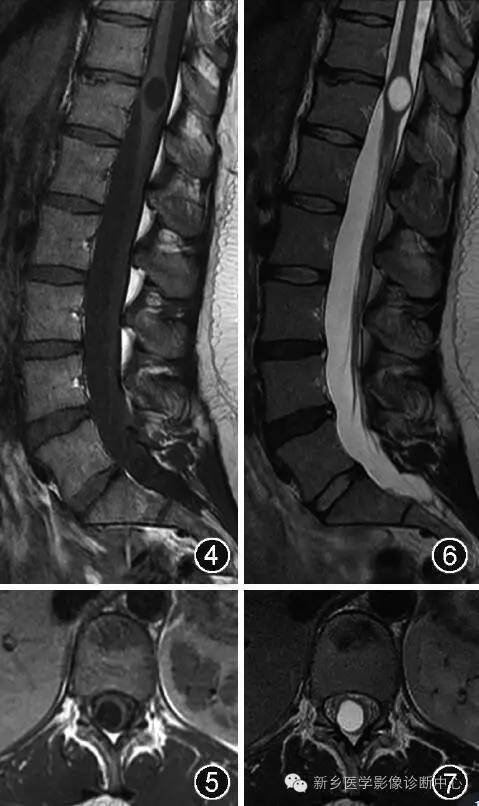

超声是诊断胎儿或新生儿第五脑室的一种常用检查方法[12](图1~3) 。 第五脑室在超声矢状切面图上显示为脊髓圆锥区域囊状扩张的低回声区并可与中央管相通 , 在超声横断切面图上表现为扩张的低回声囊腔且与周围脊髓组织有着较为清楚的分界 。 MR检查为诊断第五脑室的主要手段 。 第五脑室在MRI上通常表现为脊髓圆锥内边缘清楚的卵圆形囊腔 , 形态规则 , 囊壁光整 , 且与周围正常的脊髓组织分界清楚 , 囊内为T1WI低(图4 , 5)、T2WI(图6 , 7)高的脑脊液信号 , 囊内分隔及囊周水肿性改变比较少见 , 增强扫描后囊壁不强化 。 第五脑室需要与位于脊髓圆锥的囊性肿瘤如室管膜瘤、星形细胞瘤以及脓肿相鉴别 , 囊性肿瘤和脓肿的囊壁通常有不同程度的强化 。 脊髓圆锥的转移瘤很少见 , MRI表现通常为肿瘤强化且周围伴有明显水肿[13] 。 脊髓背侧的严重损伤也可发展为囊性病灶 , 但目前报道的大多数第五脑室病例并无外伤病史[6] 。 脊髓内的表皮样囊肿和皮样囊肿由于成分复杂导致MRI表现多变[14] , 而第五脑室的MRI表现单一 。

图4~7 男 , 45岁 。 腰椎MRI显示第五脑室是位于脊髓圆锥内且囊壁光滑的囊腔 , 囊腔内的脑脊液在矢状面T1WI上呈低信号(图4) , 在横断面T1WI上呈低信号(图5) , 在矢状面T2WI上呈高信号(图6) , 在横断面T2WI上呈高信号(图7) 。